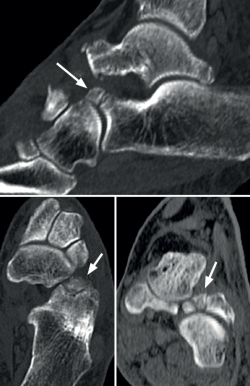

Figura 1. Imagen de tomografía computarizada (TC) donde se muestra, en los 3 planos, la presencia de un osículo secundario en la porción más dorsal de la tuberosidad anterior del calcáneo, que corresponde al os calcaneus secundarius.

En la última década del siglo XIX nacieron dos teorías. Una de ellas, de Pfitzner en 1896, sugería que las coaliciones eran debidas a la presencia de osículos accesorios situados entre dos huesos del tarso y su posterior incorporación a ellos(10). Se dedujo por la frecuente aparición de esos osículos en las mismas zonas donde suelen presentarse las coaliciones. Muchos autores apoyaron esta teoría, pues encontraban un os sustentaculum proprium en el mismo sitio donde se producían con tanta frecuencia las coaliciones de la faceta media de la articulación subastragalina, así como un os calcaneus secundarium en las coaliciones entre calcáneo y escafoides (Figura 1) y también las de la carilla subastragalina posterior, donde se asienta habitualmente el os trigonum(11). Sin embargo, esa teoría fue refutada cuando en 1955 se demostraron coaliciones tempranas en fetos en los que no habría dado tiempo al desarrollo de los osículos y su incorporación a los huesos vecinos(12).